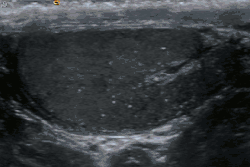

Microlitíase testicular

A microlitíase testicular é uma doença caracterizada pela presença de microcalcificações no interior dos túbulos seminíferos presentes no testículo. Sua patogênese é controversa e sua relevância clínica é incerta.[1][2]

Esta doença geralmente é descoberta incidentalmente durante a ultrassonografia do escroto. Pode ser encontrada em indivíduos normais ou em associação a uma grande variedade patologias testiculares benignas e malignas, principalmente dos tumores testiculares.[1]